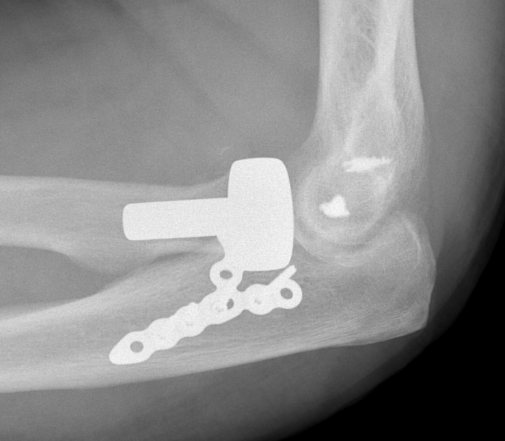

rh orif Radial Head Replacement Lateral

Type II / Reconstructable radial head Type III / Radial head arthroplasty

Lateral / Kocher / Kaplan / EDC split approach

- excise radial head

- can suture small coronoid process fracture through gap

- radial head replacement

- LCL +/- common extensor origin repair

Radial head replacement with lag screw fixation of Type II coronoid

terribleterribleterribleterrible

Radial head replacement with lasso fixation of small coronoid fragment